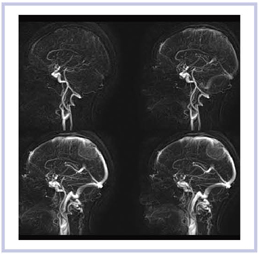

2)HOP-MRA(Hybrid of OPposite-contrast MRA)

われわれと東芝が共同開発したHOP-MRAは,同時に取得した3D-TOFの高信号からblack blood法の低信号をサブトラクションすることで血流信号を増強し,末梢動脈の描出能を向上させる新しい撮像法である。Titan 3TによるHOP-MRA(図8)では,従来の3D-TOF(a)に比べて,HOPの画像(b)で,末梢の動脈分枝の描出能が,より向上していることがわかる。冠状断方向のHOP-MRA(図9)は,バイパスの血流の開存と,さらに末梢の血管の状況が確認でき,3TによるHOP-MRAでは,きわめて良好な画像が得られている。

図8 HOP-MRA(b) 3D-TOF(a)に比較して,末梢の血管まで描出されている。

図9 冠状断方向のHOP-MRA(b)